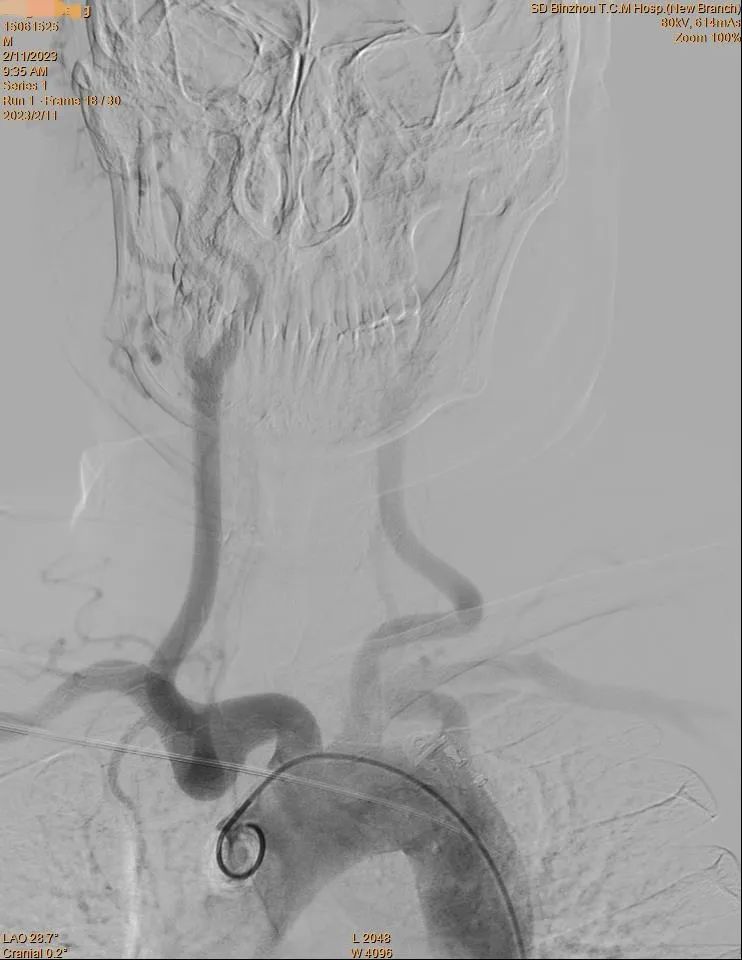

近日,滨州市中医医院(滨州医学院附属中医医院)心脑病科团队成功为一名46岁男性脑血管病患者实施全脑血管造影术,为其明确诊断,并采取相应治疗措施,受到患者高度好评。

家住滨城区的唐先生因“反复头晕1月余”入院,经我院“眩晕中心”专家联合会诊,初步确定病因是椎动脉卡压。为明确诊断,避免盲目治疗,夏乐医生为患者实施脑血管造影术检查,术中清晰了解到颅内血管情况,最终明确了唐先生的诊断,给后续的的治疗指引了方向。

脑血管造影术被誉为诊断脑血管疾病的“金标准”,近年来广泛应用于临床。局部麻醉后在导丝引导下经股动脉引入细小的造影导管,将碘影剂注入目标血管,使脑血管显影,从而了解脑血管本身的形态和病变,以及病变的性质和范围。

对于缺血性脑卒中患者,脑血管造影可以清楚地显示动脉管腔狭窄、闭塞、侧支循环建立情况等;对于脑出血患者,可进一步查明导致出血的病因,如动脉瘤、血管畸形、海绵状血管瘤等。因此,脑血管造影不但能提供病变的确切部位,而且对病变的范围及严重程度亦可清楚地了解,为手术提供较可靠的客观依据。